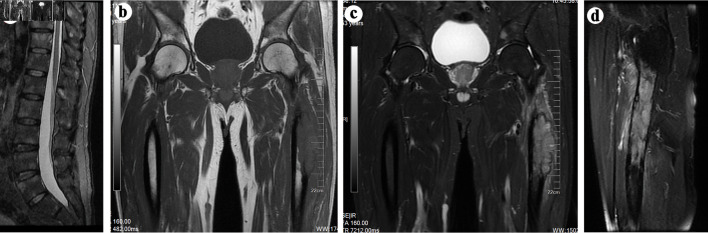

肺癌的侵袭性常常伴随着骨转移的高发病率;然而,与其他恶性肿瘤相比,肺癌引起的股骨近端转移并不常见。在本报告中,我们介绍了一名 53 岁亚洲男性的病例,他因左大腿和背部疼痛而就诊。磁共振成像显示左大腿处有严重的骨质破坏,邻近的软组织肿块也受累,成像结果与骨肉瘤相似。随后的骨活检确诊为表皮生长因子受体(EGFR)突变的肺腺癌并发骨转移。患者在服用奥希替尼后获得了生存,并接受了股骨转移手术,而没有接受肺癌姑息手术。因此,在怀疑患有骨肉瘤的患者中,应将表皮生长因子受体(EGFR)突变的肺腺癌引起的股骨近端转移作为鉴别诊断。本文介绍了表皮生长因子受体(EGFR)突变肺腺癌股骨近端转移的影像学检查结果,并讨论了其治疗方法。

The aggressive nature of lung cancer is frequently accompanied by a high incidence of bone metastasis; however, proximal femoral metastasis from lung cancer is comparatively uncommon when compared to other malignancies. In this report, we present the case of a 53-year-old Asian male who presented with pain in the left thigh and back. Magnetic resonance imaging revealed severe bone destruction with involvement of adjacent soft tissue mass at the left thigh, exhibiting imaging findings that mimic osteosarcoma. Subsequent bone biopsy confirmed the diagnosis of epidermal growth factor receptor (EGFR)-mutated lung adenocarcinoma with bone metastasis. The patient achieved survival following administration of osimertinib and underwent surgery for femoral metastases without palliative surgery for lung cancer. Therefore, proximal femoral metastasis from EGFR-mutated lung adenocarcinoma should be considered as a differential diagnosis in patients suspected to have osteosarcoma. The imaging findings of proximal femoral metastasis from EGFR-mutated lung adenocarcinoma were presented, and their therapeutic management was discussed.